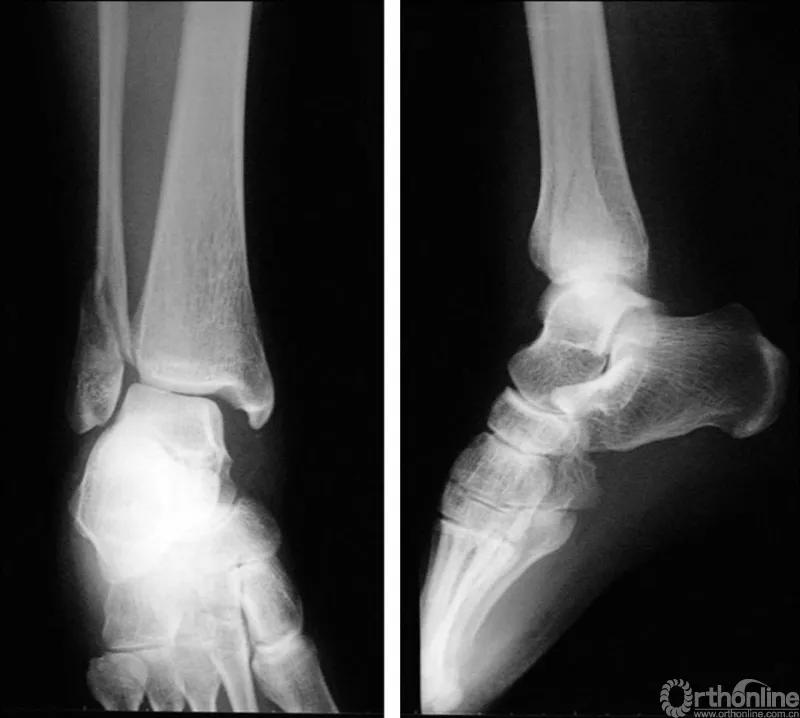

当踝关节严重损伤时内外踝及距骨将发生不同程度的移位(图8)。有时外踝骨折会伴有三角韧带的损伤,静态的X线摄片并不能准确地反映踝关节的稳定性,应力位片及MRI检查可完善对踝关节稳定性及韧带损伤的评估(图9)。此时应通过患肢损伤机制及放射资料准确判断踝关节损伤的类型以正确指导复位和固定。有时单纯内踝骨折可能是更为复杂的“Maisonneuve骨折”的一部分,该骨折还包括腓骨近端骨折及韧带联合损伤,故X线检查应投照整个胫腓骨。

图8 骨折移位明显合并有脱位